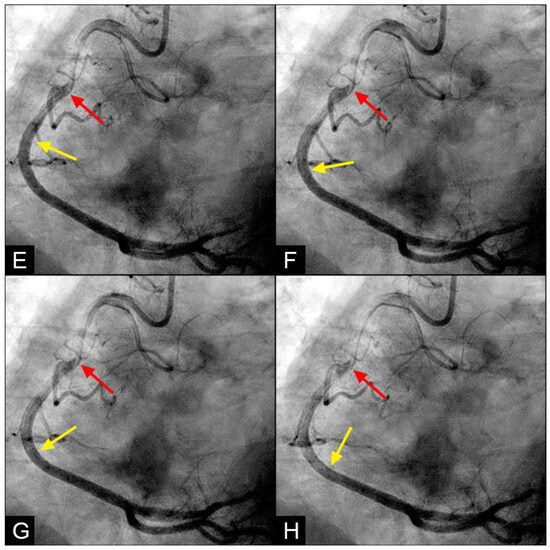

In the right coronary artery (RCA), with the novel angiographic technique, during diastole, the antegrade flow was clearly illustrated (Figure 9A–D). The leading edge of the flow was sharp, suggestive of laminar flow (Figure 9C). The speed in diastole was fast, as the blood could traverse from the end of the proximal segment to halfway through the mid-segment in just 0.067 s, equivalent to one image interval (Figure 9D). At this junction, at the onset of systole, the antegrade flow decelerated (yellow arrow), while the mixed black contrast persisted at the location of the transition from diastole to systole (red arrow). This contrast remained until near the end of systole, providing visual evidence of disorganized flow secondary to the interaction between the retrograde and antegrade flows; most likely, it was a collision (Figure 9E–H) (Video S2).

Figure 9.

(A–D) Collision in the RCA. This is a series of eight consecutive images of an angiogram of the right coronary artery (RCA). (A) The artery is filled with contrast. There is a moderate lesion at the mid-segment. (B) The blood (white) is seen entering the ostium of the RCA (arrow). This is the beginning of diastole. (C) The blood (white) is seen at the outer border of the first curve of the RCA (yellow arrow). (D) The blood (white) moves to the mid-segment of the RCA (yellow arrow). (E–H) Collision during the transition to systole. (E) The blood is seen reaching the mid-segment of the RCA (yellow arrow) at the end of diastole and beginning of systole. Here, the blood (white) is mixed with the contrast (black), seen as a random, disorganized black-and-white pattern (red arrow). This is the visual imaging of turbulent flow. (F,G) The contrast (black) concentrates at the mid-segment, at the collision line (red arrow). The contrast is also seen darker in the proximal segment, suggestive of retrograde flow. The antegrade flow still moves forward slowly (yellow arrow). (H) The blood is seen reaching the beginning of the distal segment (yellow arrow). The turbulent flow (mixing black contrast and white blood) is still seen prominently at the collision site, and the retrograde flow is lighter at the mid-segment (red arrow).